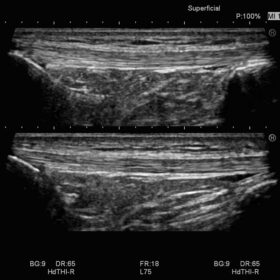

The art of effective imaging – HI VISION imaging capability offers customised scanning parameters combined with high-speed image processing to facilitate efficient & accurate diagnoses. Proven innovative technologies confer superior penetration, temporal, spatial and contrast resolution giving high quality images for every patient every time.

- New Image Formats – Imaging outside the Box